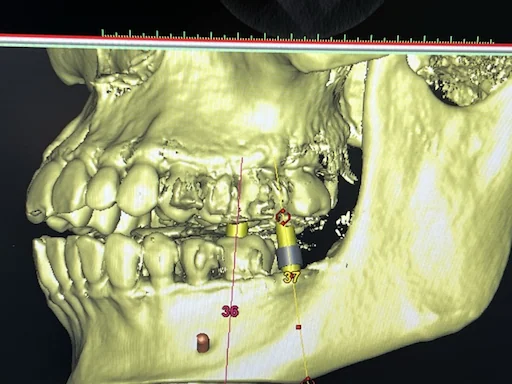

Patientenfall 36, 37 - Implantatplanung

Schritt 2

Somit wurden zwei Einzelzahnimplantate in Regio 36, 37 geplant.